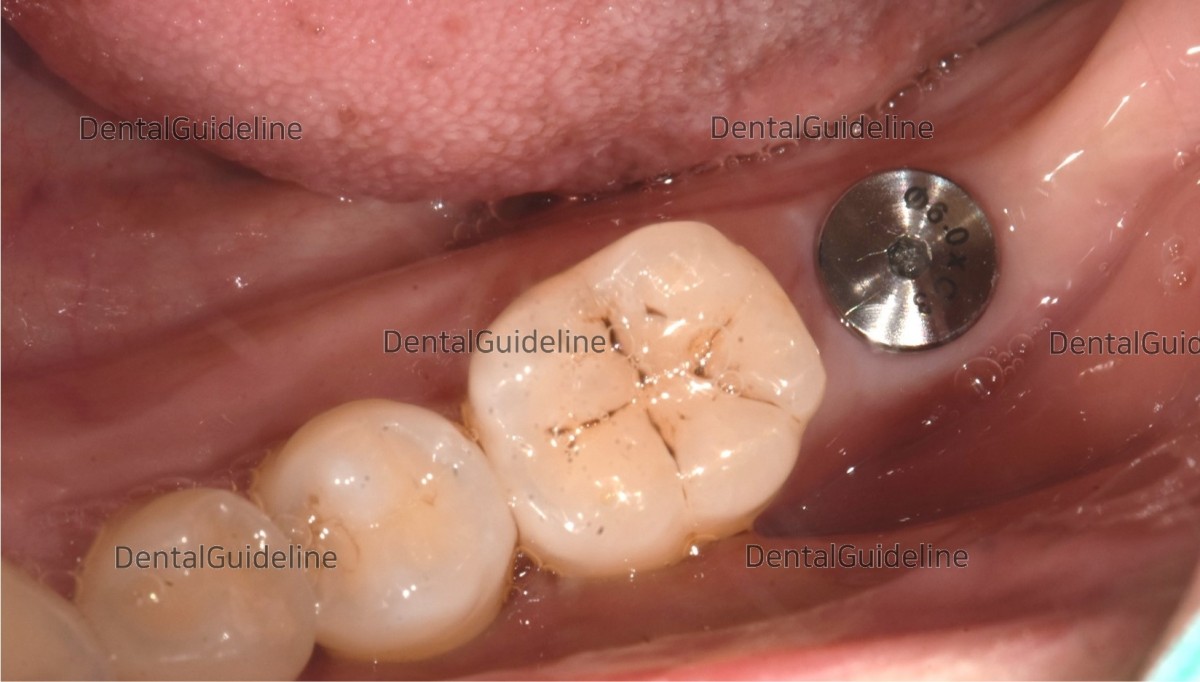

1. Intraoral view before surgery

9. Post-op 10week, intra-oral photo on the day of uncovery.

10. A linear incision was given on the attached gingiva to secure the attached gingiva.

11. Healing Abutment engagement by expanding soft tissue to form the dense sulcus of the gingiva.